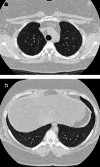

Objectives: Pulmonary Langerhans cell histiocytosis (PLCH) is a rare interstitial granulomatous disease that usually affects young adults who are smokers. Chest computed tomography (CT) allows a confident diagnosis of PLCH only in typical presentation, when nodules, cavitated nodules and cysts coexist and predominate in the upper and middle lungs.

Results: PLCH can present with some aspecific features that may cause diagnosis of the initial disease to be overlooked or other pulmonary diseases to be suspected. In cases of nodule presentation alone, the main differential diagnosis should include lung metastasis, tuberculosis and other infections, sarcoidosis, silicosis and Wegener's disease. In cases of cysts alone, the most common diseases to be differentiated are centrilobular emphysema and lymphangiomyomatosis. Clinical symptoms are usually non-specific, although a history of cigarette smoking, coupled with the presence of typical or suggestive findings at imaging, is key to suspecting the disease. Atypical presentations require surgical biopsy for diagnosis.

Teaching points: • PLCH is a rare interstitial smoking-related disease that usually affects young adults. • The typical first CT shows a mix of nodules, cavitary nodules and cysts in the upper-middle lungs. • Atypical appearance, either cysts or nodules alone, mandates that other diagnoses be considered. • Lung cystic involvement correlates with lung function abnormalities and predicts functional decline. • Integration of the clinical history and imaging results is key to diagnosis.